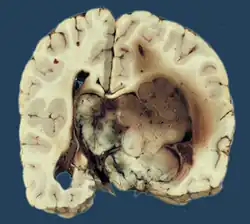

Choroid plexus papilloma, also known as papilloma of the choroid plexus, is a rare benign neuroepithelial intraventricular WHO grade I lesion found in the choroid plexus.[1] It leads to increased cerebrospinal fluid production, thus causing increased intracranial pressure and hydrocephalus.[2]

Choroid plexus papilloma occurs in the lateral ventricles of children and in the fourth ventricle of adults. This is unlike most other pediatric tumors and adult tumors, in which the locations of the tumors is reversed. In children, brain tumors are usually found in the infratentorial region and in adults, brain tumors are usually found in the supratentorial space. The relationship is reversed for choroid plexus papillomas.

Choroid plexus tumors are divided into three categories by the World Health Organization (2016):[9] papillomas (grade I), atypical tumors (grade II), and carcinomas (grade III). Less than two mitotic figures per 10 high power fields are present in CPPs, two to five are present in atypical ones, and more than five are present in carcinomas. The tumors are visible as pink, soft, spherical lumps with erratic projections and considerable vascularity.

The tumor is neuroectodermal in origin and similar in structure to a normal choroid plexus. They may be created by epithelial cells of the choroid plexus. Papillary fronds lined by bland columnar epithelium are visible under the microscope. Normal absences include mitotic activity, nuclear pleomorphism, and necrosis.[10] Tumors have positive immunohistochemistry for cytokeratin, vimentin, podoplanin, and S-100.[11] Up to 20% of choroid plexus papilloma patients may test positive for glial fibrillary acidic protein (GFAP).[12] Studies have found that fourth ventricle cancers express more S100 than lateral ventricle tumors, and older patients (over 20 years) express more GFAP and transthyretin than younger patients.[13] Some individuals with choroid plexus papilloma have germline TP53 gene mutations, according to genetic analyses.[14] These cancers rarely exhibit nuclear p53 protein positivity. Aicardi syndrome, hypomelanosis of Ito, and 9p duplication are syndromic correlations of choroid plexus papilloma.